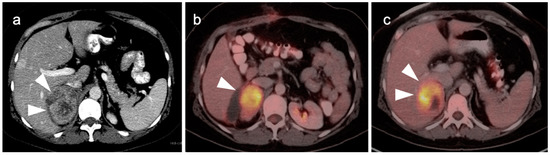

4. Hepatocellular Carcinoma

8. Pancreatic Carcinoma